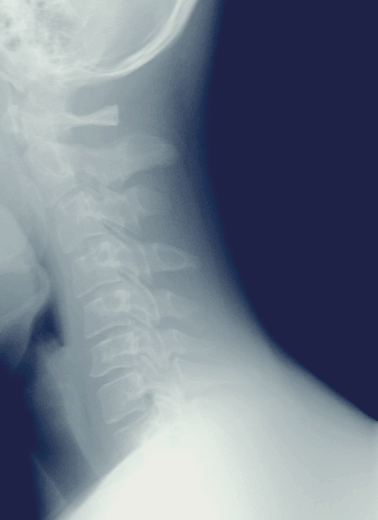

머리 무게는 대략 3~6Kg 정도입니다. 무거운 머리를 지탱하는 목 근육과 뼈는 자세에 따라 각각 받는 부담이 달라집니다. 이런 부담을 피하기 위해 원래 목의 경추는 C자형의 커브를 가지고 있습니다. TV나 모니터 등을 오래 바라보고 있으면 자기도 모르게 얼굴이 앞으로 나가고, 목에 가는 부담을 나누기 위해 자세가 달라지게 됩니다. 앞으로 나간 무게의 하중을 받치고자 목은 C자 커브에서 일자로, 앞으로 나가게 됩니다. 이 모양이 마치 거북이 같이 목이 짧게 보여 거북목 증후군이라고 부르게 되고, 이를 일컬어 일자목 증후군이라고 합니다. 최근에는 스마트폰의 보급이 일자목의 가장 큰 원인이 되고 있습니다. 한번 자리 잡은 근육과 뼈는 원래의 자리를 지키려고 하기 때문에 한번 일자목이 되면 다시 원래의 모습으로 돌아가기 힘들어 많은 사람들이 치료에 애를 먹고 있습니다.

① 먼저 의심이 된다면 근처의 정형외과를 방문하셔서 X-Ray 사진을 찍어 보시는 것을 추천드립니다. 현재 일자목의 진행사항을 확인하고 고통이 있다면 물리치료 등으로 호전시킬 수도 있습니다.